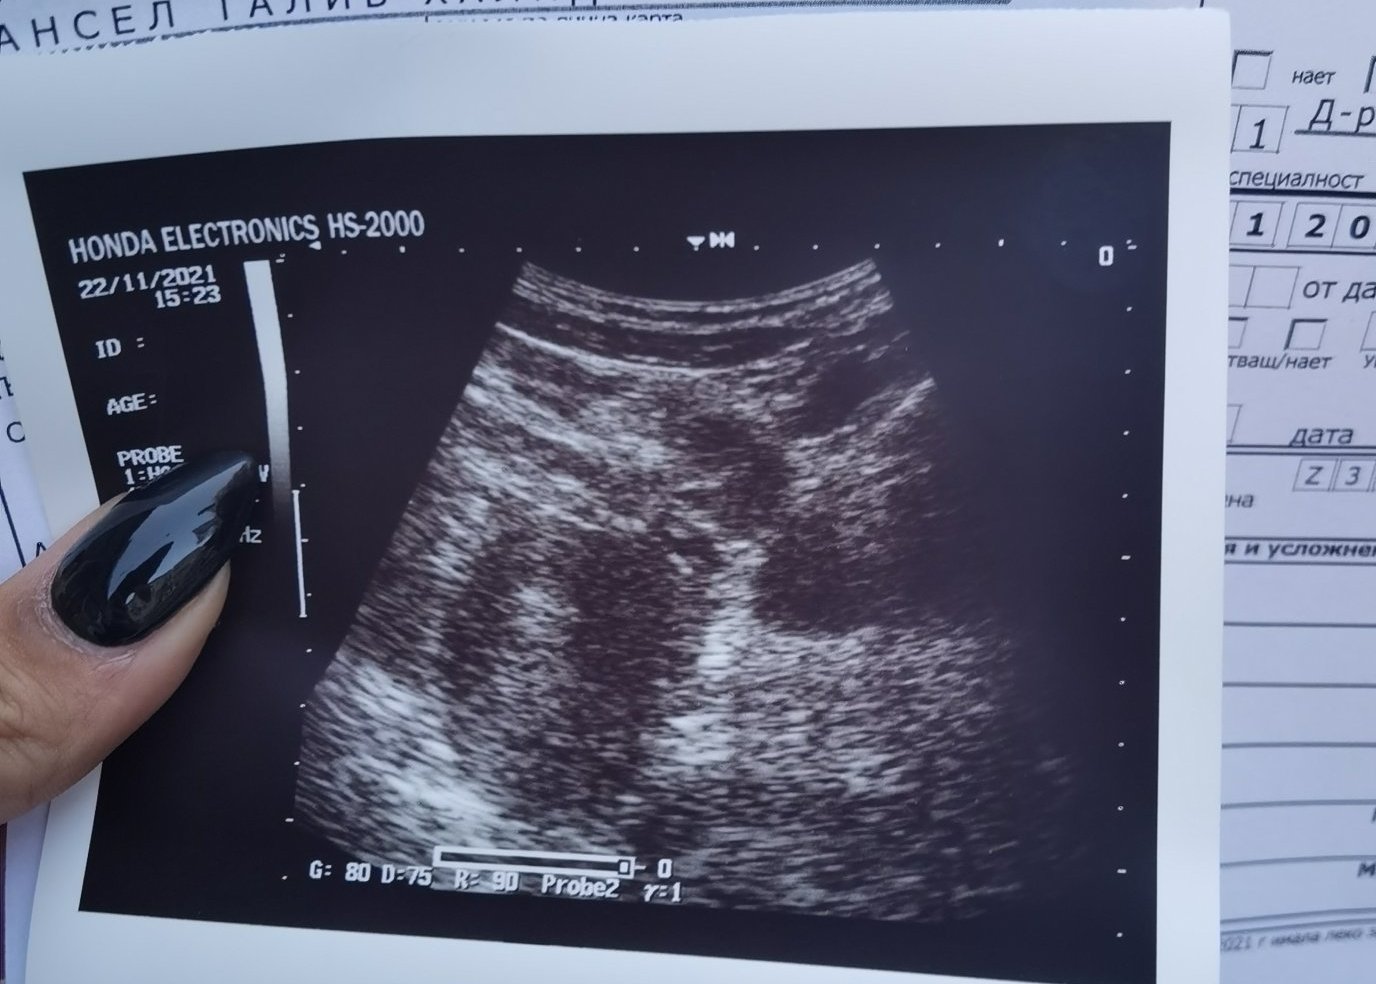

• Мнения: 1 978

На коремен при това ЧХГ нищо не се вижда. Той мисля засича при ЧХГ над 10000. Ако искате да видите дали плода е където трябва и отговаря на гестационния си срок в толкова ранна бременност, прегледа е с вагинален видеозон. Иначе просто са догадки според дебелината на лигавицата на матката и резултата ви от ЧХГ. Simple Smile Стискам палци всичко да е наред. Снимка от вагинален в 6+3 за да видите как изглежда плоден сак

Здравейте виждате ли нещо, доктора виждал плоден сак, но аз не виждам. 😁Чхг днес 1448. Притеснявам се да няма извънматочна, не знам защо..

аз виждам плоден сак